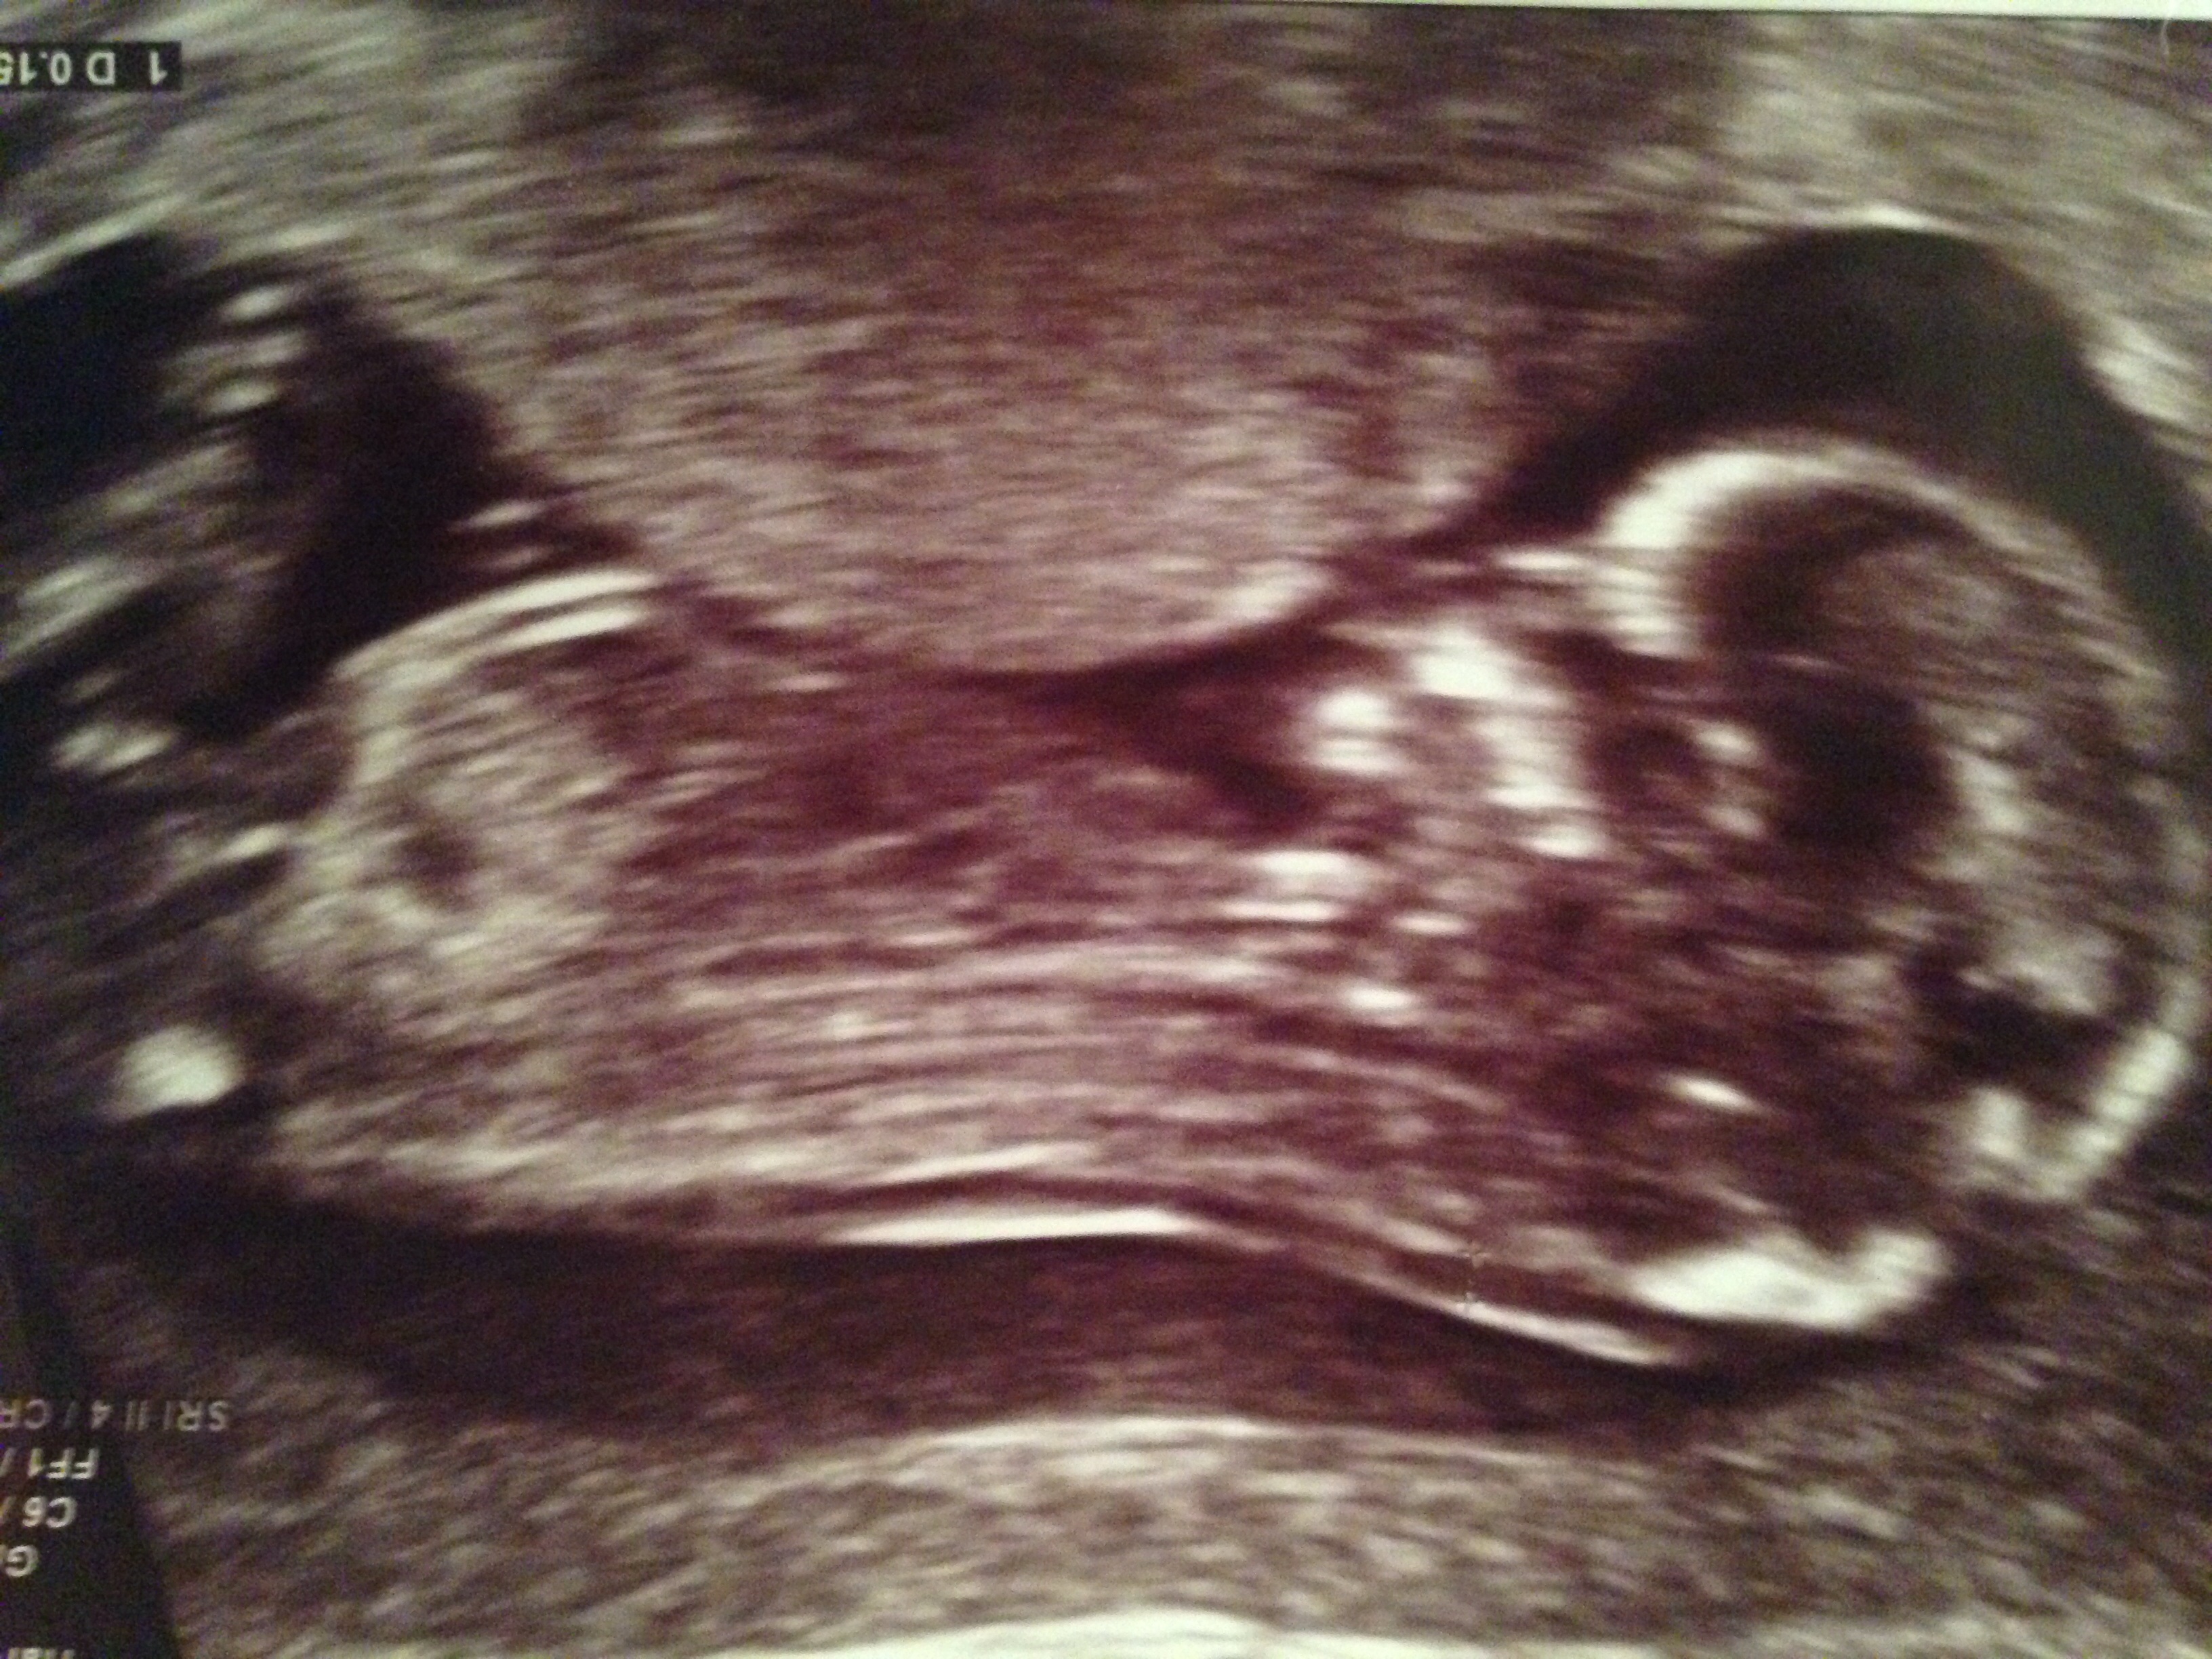

Okay, so I had my 13 wk ultrasound. I have an awesome doc who has been doing this for like 20 years. He's called the "baby whisperer" in my area. He said that he is 75% sure I'm having a boy. I've attached a photo with what I believe is a nub. Those who are familiar with this theory... What do you think?